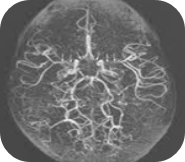

모야모야병은 뇌혈관이 서서히 좁아지며 막히는 희귀한 뇌혈관 질환으로, 뇌에 혈액 공급이 부족해지는 심각한 상태를 초래합니다. 이 질환은 일본어 "모야모야"에서 유래했는데, 이는 "연기가 피어오르는 모양"을 뜻합니다.

뇌혈관 조영술에서 좁아진 혈관 주변에 작은 측부 혈관들이 마치 연기처럼 보이는 모습이 특징이기 때문입니다. 주로 한국, 일본 등 동아시아에서 발병률이 높으며, 소아와 성인 모두에게 영향을 미치는 질환입니다. 소아에게는 뇌허혈이나 뇌경색으로, 성인에게는 뇌출혈로 나타나는 경우가 많아 나이에 따라 증상이 다르게 나타나는 점이 특징입니다.

모야모야병은 MRI, MRA(자기공명 혈관조영술), 뇌혈관 조영술, SPECT 같은 검사로 진단합니다. 이 검사들은 단순히 질환을 확인하는 데 그치지 않고, 병의 진행 정도와 수술 필요성을 판단하는 데도 사용됩니다. 현재 모야모야병은 불치병으로 분류되며, 근본적인 치료법은 없지만 증상을 완화하고 합병증을 예방하는 치료는 가능합니다.